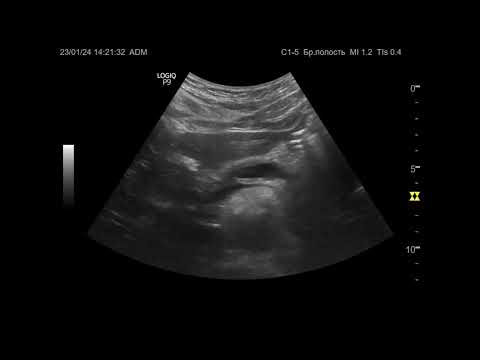

Ультразвуковая диагностика (УЗИ). Доктор Иогансен. Видеопримеры. Выпуск 58. Панкреатолитиаз.